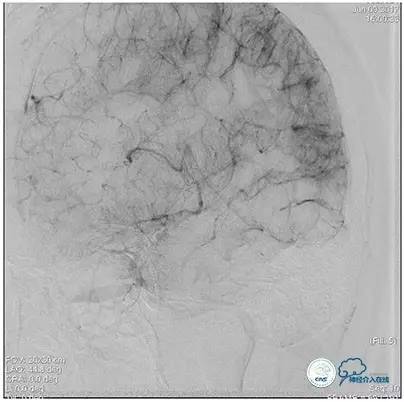

术中造影

5ml/s,总量8ml,压力100~150